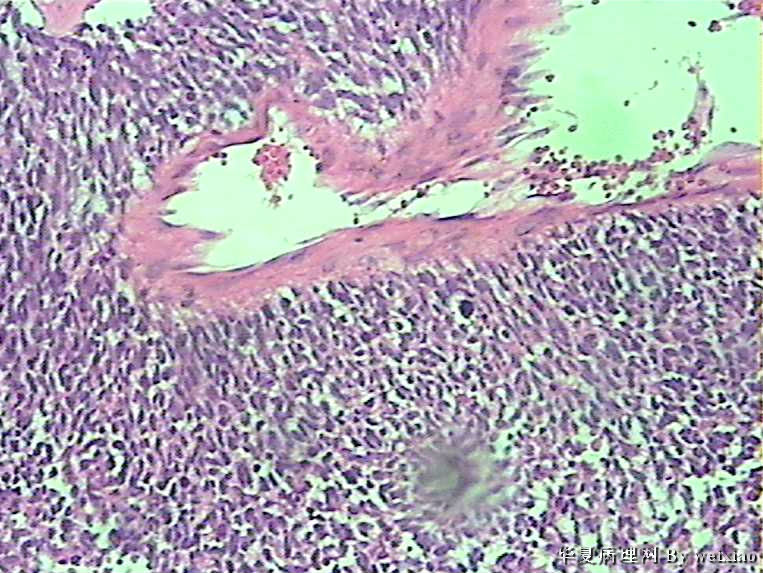

额叶肿瘤

病史:男45岁,头痛2个月,手术所见:额叶占位性病变,与周围正常脑组 织的界限不清。

大体:灰白色碎组织一堆,质软,大小:2.5*1.8*1.3cm

参考诊断

胶质母细胞瘤